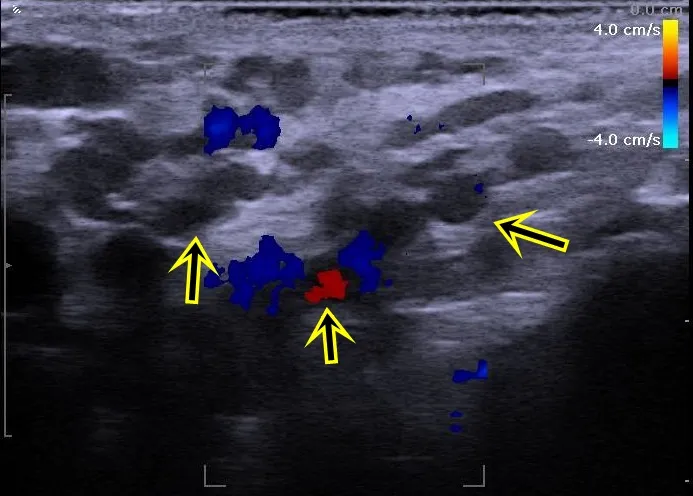

呂謹亨為鮑先生進行身體理學檢查及陰囊超音波檢查,發現左側的陰囊外觀靜脈叢明顯鼓起,陰囊超音波顯示靜脈擴張直徑超過3.5mm,靜脈血流亂流與逆流情況嚴重,確診為第四度精索靜脈曲張,配合精液檢查報告,建議進行微創精索靜脈曲張顯微手術,手術順利,住院3天即出院。

箭頭所指處即為精索靜脈屈張並血液亂流。院方提供